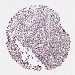

UROTHELIAL CANCER - Protein expressioni

A mouse-over function shows sample information and annotation data. Click on an image to view it in a full screen mode. Samples can be filtered based on level of antibody staining by selecting one or several of the following categories: high, medium, low and not detected. The assay and annotation is described here.

Note that samples used for immunohistochemistry by the Human Protein Atlas do not correspond to samples in the TCGA dataset.

Antibody stainingi

Antibody staining in the annotated cell types in the current human tissue is reported as not detected, low, medium, or high, based on conventional immunohistochemistry profiling in selected tissues. This score is based on the combination of the staining intensity and fraction of stained cells.

Each image is clickable and will lead to virtual microscopy that enables deeper exploration of all samples and also displays staining intensity scores, fraction scores and subcellular localization as well as patient and tissue information for each sample.

Antibody HPA038450

Antibody HPA038451

Staining

High

Medium

Low

Not detected

Intensity

Strong

Moderate

Weak

Negative

Quantity

>75%

75%-25%

<25%

None

Location

Nuclear

Cytoplasmic/membranous

Cytoplasmic/membranous,nuclear

Urothelial carcinoma, High grade

Urothelial carcinoma, Low grade

Urothelial carcinoma, NOS